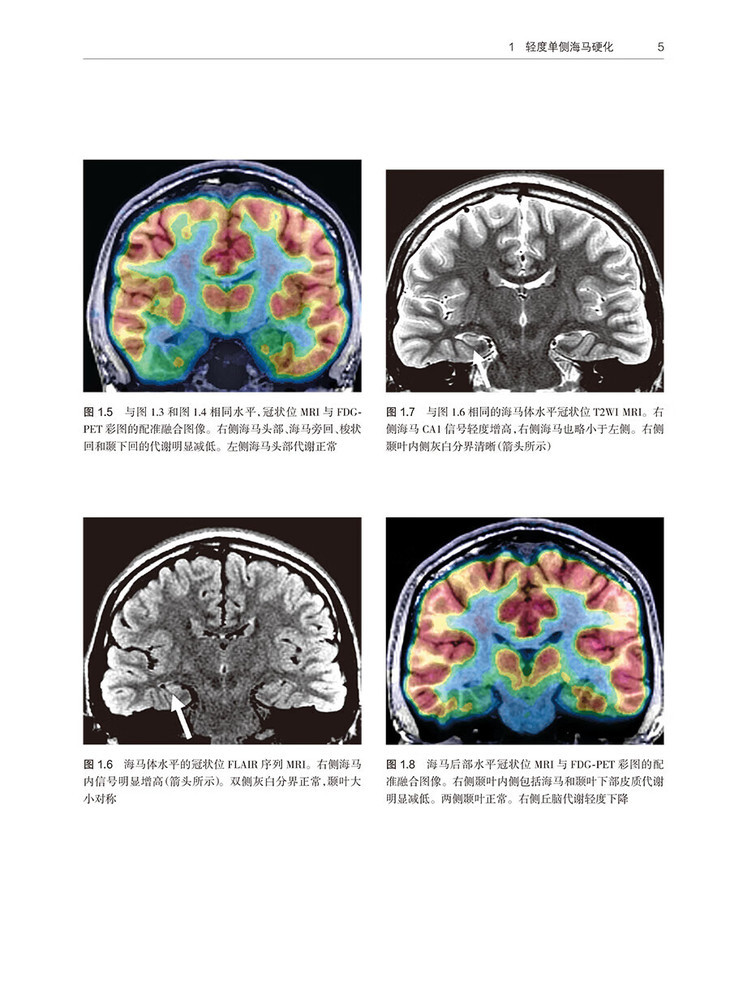

1 轻度单侧海马硬化 /3